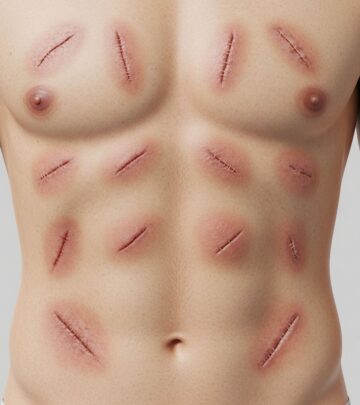

Clinically, fibrosarcoma manifests as a slowly enlarging, painless subcutaneous or dermal nodule, often on the trunk, extremities, or head. Early lesions may appear plaque-like or indurated, progressing to protuberant nodules measuring 1–5 cm or larger. Skin changes include erythema, telangiectasia, or ulceration in advanced cases. Pain, tenderness, or neurological symptoms arise with deep invasion. In infantile cases, rapid growth is noted within weeks of birth. Differential clinical considerations include DFSP, leiomyosarcoma, and benign fibrous histiocytoma. Incidence is low, approximately 1–2% of adult soft tissue sarcomas.

- Slow-growing firm nodule or plaque on trunk/extremities

- Potential for local recurrence and metastasis (lungs, bones)